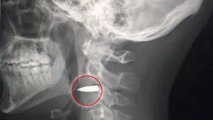

Atteint d'une balle dans le cou, il survit miraculeusement